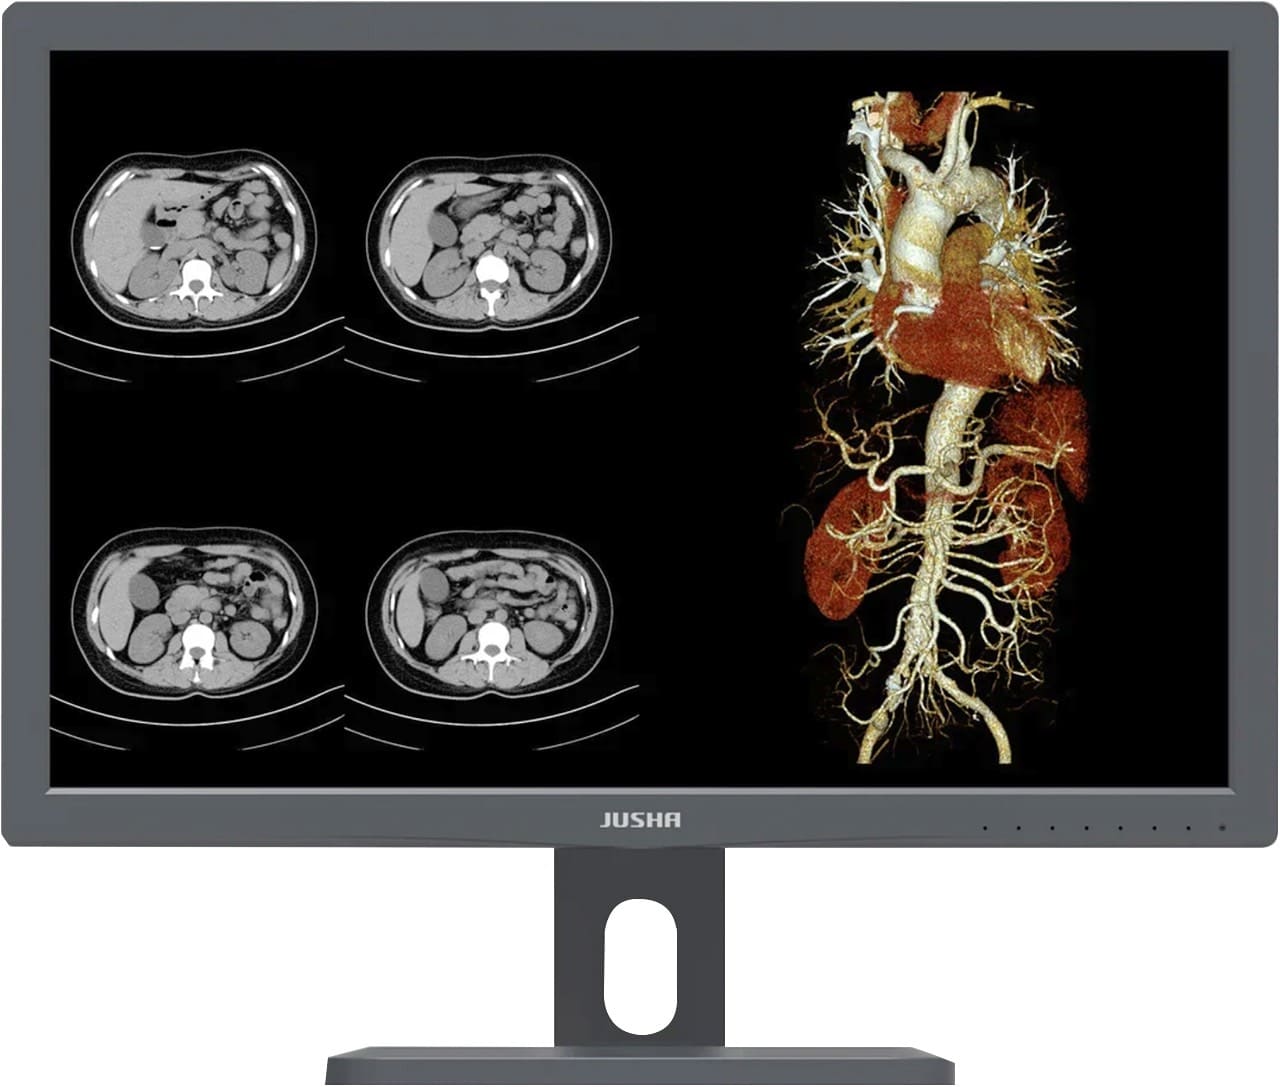

Медицинский монитор — это монитор, который отвечает высоким требованиям к медицинской визуализации в радиологии и маммографии. Он используется рентгенологами для просмотра диагностических изображений, таких как рентгеновские снимки, данные магнитно-резонансных исследований и компьютерной томографии и многое другое. Диагностические дисплеи поставляются со специальными средствами и технологиями, которые помогают рентгенологам быстро и точно поставить диагноз.

Профессиональный медицинский монитор Jusha обладает высоким разрешением, высокой яркостью и 16-битными оттенками серого (уровень 65 536), встроенным DICOM стандарт LUT, обеспечивает требовательный клинический диагноз, как: PACS, цифровая маммография CR, DR и другие радиационные систем

Яркость профессионального медицинского дисплея JUSHA может достигать 600 кд / м 2 . Благодаря сочетанию высокой яркости и отличного контраста создается значительное ощущение глубины, идеально подходящее для определения местоположения очагов.